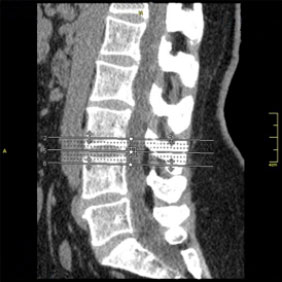

Tomografía computarizada Columna

< Volver a "Tomografía Computarizada (TC) con Inteligencia artificial"Con esta prueba valoraremos la patología de las vertebras, fracturas, hernias, protusiones discales,…